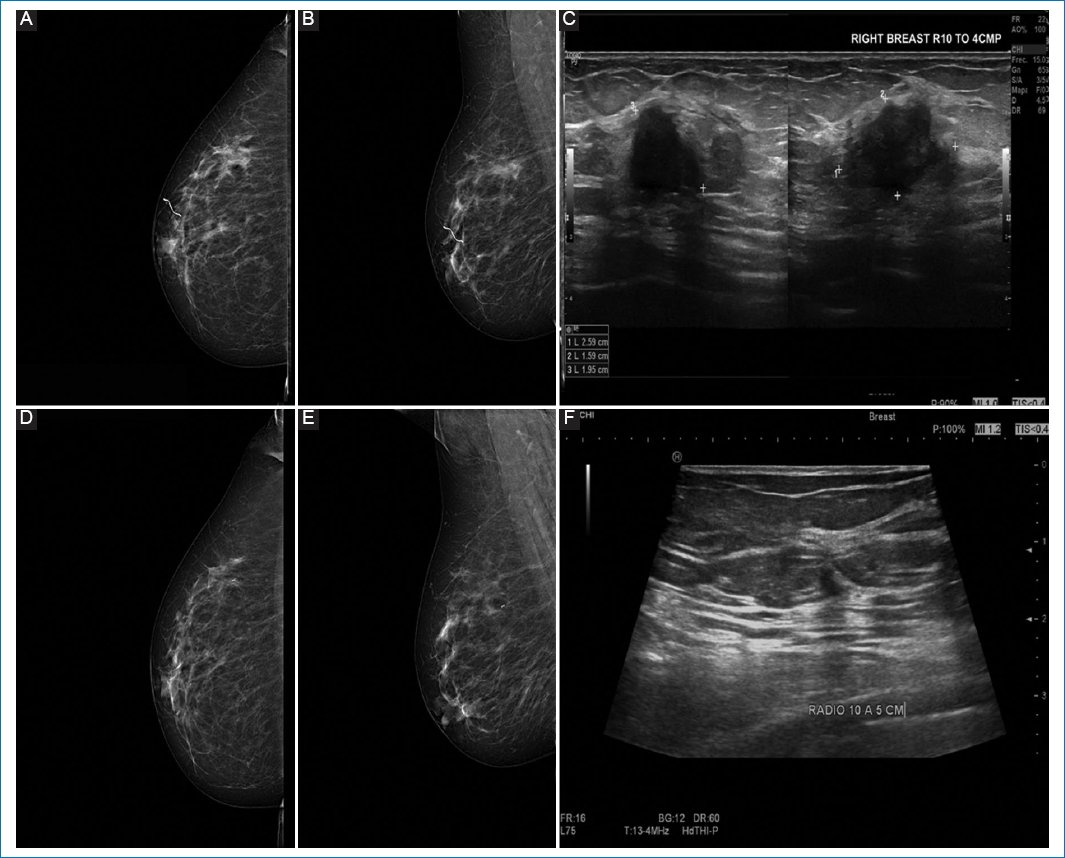

Pathologic response by imaging was classified as partial in 55.8% of cases (Figs. 1 and 2), complete in 34.6% (Figs. 3 and 4), stable (Fig. 5), or progressive disease in 9.6%. By pathology (RCB), response was complete in 53.8%, partial in 34.6%, and progressive in 11.5% (Fig. 6).

Figure 1. A-C: pre-neoadjuvant images. D-F: post-neoadjuvant images. 51-year-old woman diagnosed with left breast cancer, clinical stage IIA by T2N0M0, Luminal B, estrogen receptor 60%, PR 90%, with human epidermal growth factor receptor 2 overexpressed, Ki67 45%. A and B: pre-neoadjuvant mastography specimen, with irregular nodule, in upper outer quadrant. C: ultrasound same patient with irregular nodule in R12 at 50 mm, from the nipple. D and E: mastography. F: ultrasound showing a reduction > 20%, which corresponds to partial response.